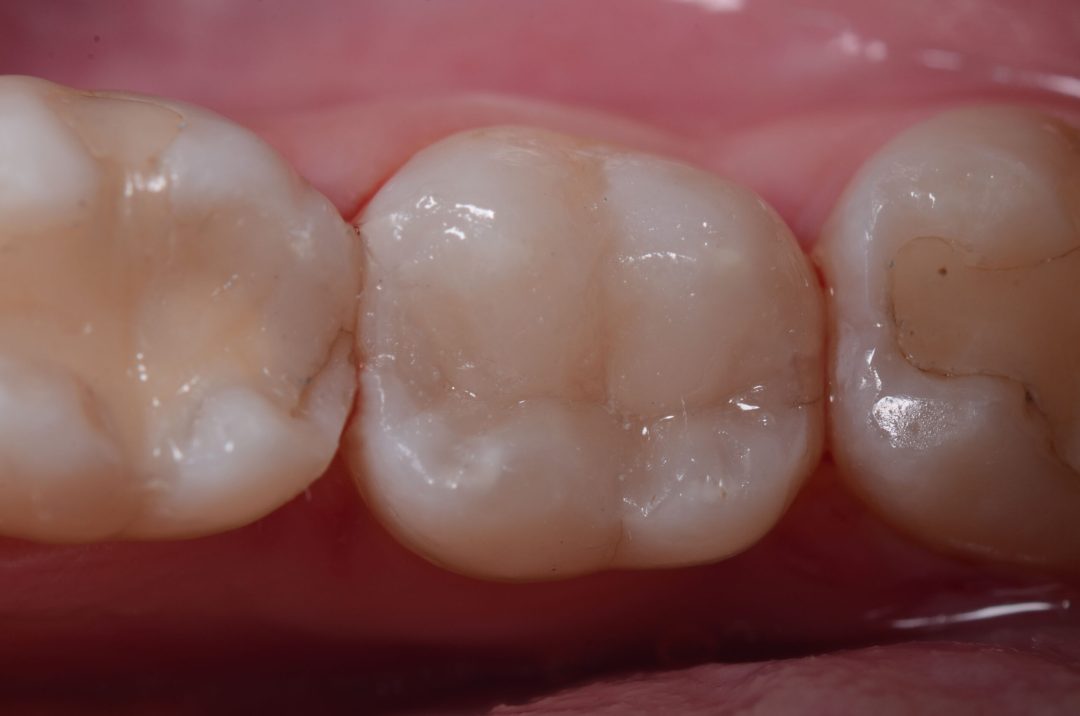

Following that, the universal chroma composite Vittra APS Unique was applied in layers (since it is not a bulk-fill type composite) rebuilding the anatomy. This composite is very interesting because, in the beginning, before polymerization, the composite looks opaque and whitish. However, after photoactivation, the composite takes the color of the side walls of the tooth, integrating itself chromatically with the dental structure in a perfect way, allowing for the mimicking and a fantastic esthetic result, in a simple way, with just one composite. This new universal chroma composite came to revolutionize and, above all, simplify and facilitate, with extreme esthetic quality, restorative technique and procedures.